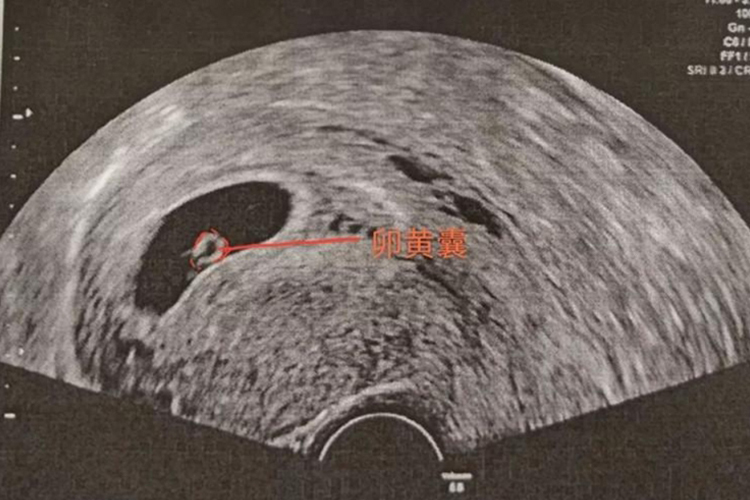

15天的胚胎的胚龄处于2-3周之间,已成为二胚层胚盘,向三胚层胚盘发育,长度为0.1-0.4mm,外层包裹卵黄囊。

妊娠第10周(受精后8周)内的胚体称为胚胎,是主要器官完成分化的时期。15天的胚胎的胚龄处于2-3周,胚龄2周时胚囊形态为圆形二胚层胚盘,此时植入子宫内膜的过程完成,绒毛膜形成,长度为0.1-0.4mm。二胚层时期囊胚着床后,内细胞团继续增生和分化,形成羊膜囊和卵黄囊。胚龄3周时胚囊形态为梨形三胚层胚盘,胚胎的神经板和神经褶出现,体节初现,长度为0.5-1.5mm,15天的胚胎形态处于两者之间。